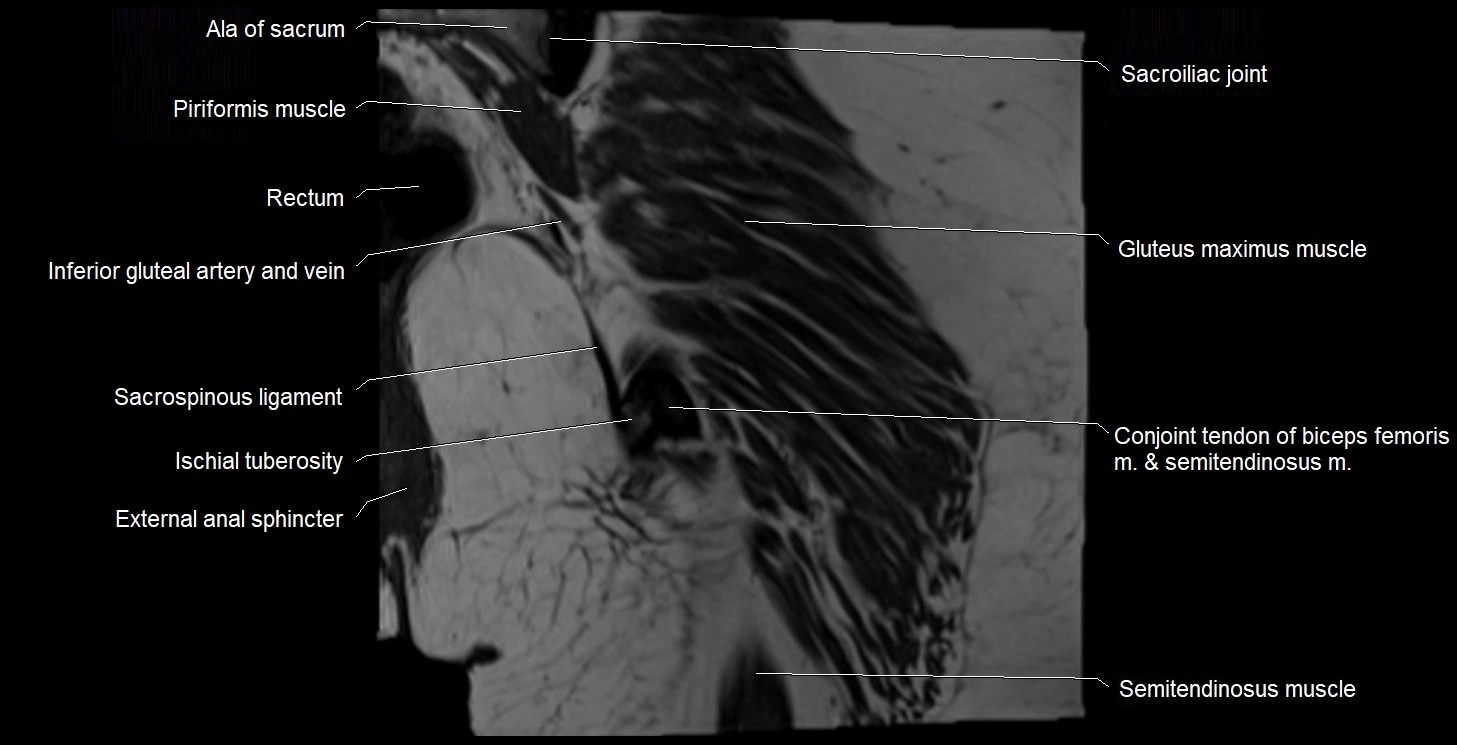

- Ala of sacrum

- Conjoint tendon of biceps femoris & semitendinosus

- External anal sphincter

- Ischial tuberosity

- Rectum

- Sacroiliac joint

- Sacrospinous ligament